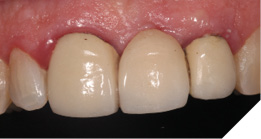

The definitive metal ceramic bridge was fabricated with the new soft tissue emergence profiles. The framework was fabricated by Creates and due to the short nature of the span we felt the intraoral scan was sufficiently accurate without the need for a verification jig to ensure passive framework fit into the implant fixtures. The ceramic work was optimally shaped for cleans ability and long-term soft tissue adherence and maintenance.

The definitive bridge was fitted and torqued in situ uneventfully after such excellent healing of the provisional bridge (Figs. 31-37).

Final result

The definitive bridge has integrated well and both hard and soft tissue healing has gone well and very predictably. The chosen biomaterials have integrated well and healed exactly how we would expect them to. The patient was very happy with the aesthetic result especially when we consider what he had been used to preoperatively. The function and phonetics met the patient’s expectations and overall, we were all very happy with the result.